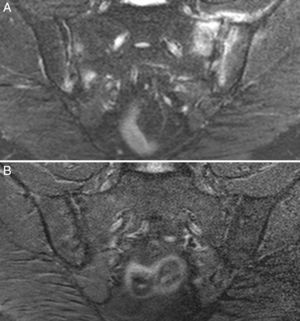

Caso 3: mujer de 50 años, diagnosticada de espondilitis anquilosante hacía 3 años, con sacroilitis bilateral en radiografía simple y HLA B27 positivo. Tenía dolor lumbar inflamatorio severo invalidante y refractario, con insuficiente respuesta a antiinflamatorios no esteroideos, y con difícil manejo debido a la coexistencia de obesidad, espondiloartrosis, hipertensión arterial, alteración crónica de transaminasas, diabetes mellitus, hipotiroidismo autoinmune y diarrea. El dolor condicionaba una vida limitada a uso de muletas y silla de ruedas, con dependencia de otros para su cuidado personal. La ileocolonoscopia con biopsias de íleon y colon fue normal. La RM de sacroiliacas mostraba marcado edema óseo demostrativo de sacroilitis. La serología de cribado de EC fue negativa; el HLA mostró DQ5 homocigoto con ausencia de DQ2 y DQ8. Se ofreció la posibilidad de hacer biopsia duodenal, pero la paciente optó por intentar la DSG sin hacer biopsia duodenal. La evolución con DSG y suplementos de vitamina D fue muy favorable, con remisión del dolor lumbar invalidante y de la diarrea a los 7 meses. Persistía lumbalgia mecánica y astenia. Se añadió dieta sin lácteos con mejoría de la astenia. En la RM de sacroiliacas realizada a los 17 meses de seguimiento se observó remisión del edema óseo (fig. 3). Había recuperado vida activa normal y vuelto a trabajar. No volvió a tomar gluten.

Estos 4 pacientes tienen espondiloartritis axial, 2 de ellos con espondilitis anquilosante y uno con espondiloartritis psoriásica. Son sensibles al gluten, con clara respuesta clínica a la DSG a pesar de haberse descartado la EC. En 2 casos hay un familiar celíaco. La mejoría del dolor lumbar crónico ha sido muy relevante, hasta el punto de la resolución del cuadro clínico, y en un caso se observa remisión del edema en la RM de sacroiliacas tras un largo tiempo de seguimiento. Además, en los 3 pacientes en que ha habido exposición al gluten, esta ha ido seguida de recidiva clínica. Es improbable que una mejoría clínica como la descrita sea debida a casualidad o a efecto placebo. La observación de la linfocitosis intraepitelial junto con la evolución clínica apoya el concepto de espondiloartritis enteropática por SGNC. La figura 4 muestra las biopsias duodenales de los casos 1, 2 y 4, en las que se observa un aumento de los linfocitos dentro del epitelio intestinal.

Biopsias duodenales tras tinción inmunohistoquímica para CD3 en las que se evidencia un aumento del número de linfocitos intraepiteliales, sin acortamiento vellositario ni hiperplasia de criptas. A) Aumento del número linfocitos intraepiteliales a lo largo de la vellosidad intestinal (20×), caso 1. B) Detalle del incremento de linfocitos intraepiteliales (40×), caso 2. C) Detalle del cúmulo de linfocitos intraepiteliales en el ápice de la vellosidad intestinal (40×), caso 4, cortesía del Dr. Fernando Casco, Histocitomed.